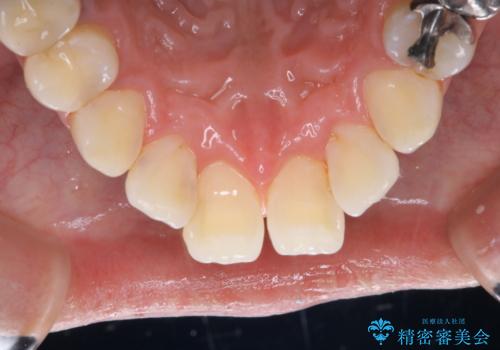

PMTC60分コースを行いました。

半年に一度クリーニングしているとのことでした。タバコとコーヒーの着色でした。

着色に厚みがあるため、エアーフローも使用して除去しました。

エアフローとは、歯面清掃を行う器具の一種で、非常に細かなパウダーを強力なジェット水流で歯に吹き付け汚れを落とす器具です。水圧とパウダーの力で隅々まで着色やバイオフィルムを効果的に、そして短時間で落とすことができます。